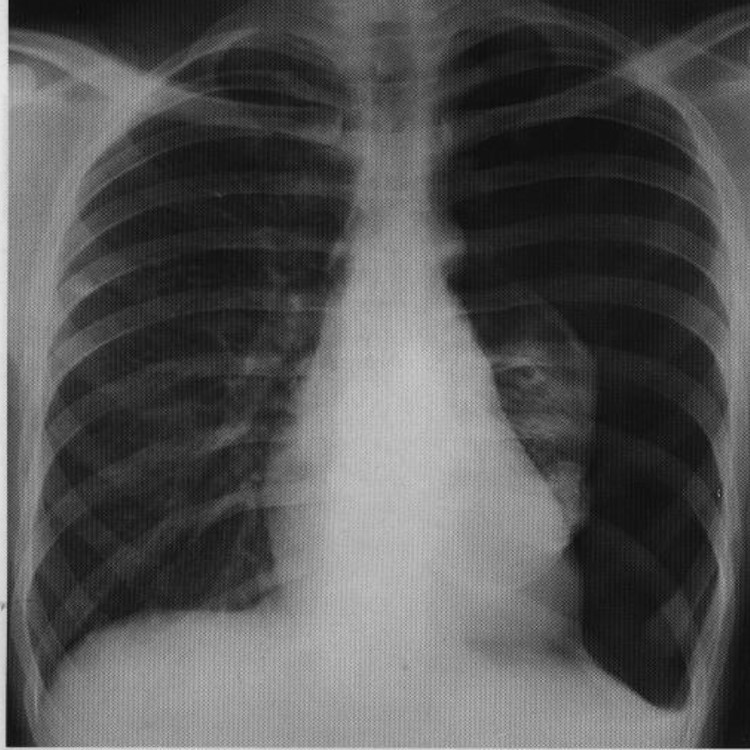

60yo female with history of congestive heart failure presents to the clinic with a 3 week history of worsening SOB

View

DX

DX: pleura effusion